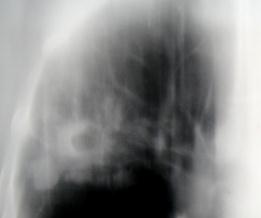

Рис.2. Инфильтрат. Просветление обозначает наличие деструкции (стрелка). Вокруг – множество очагов бронхогенного отсева